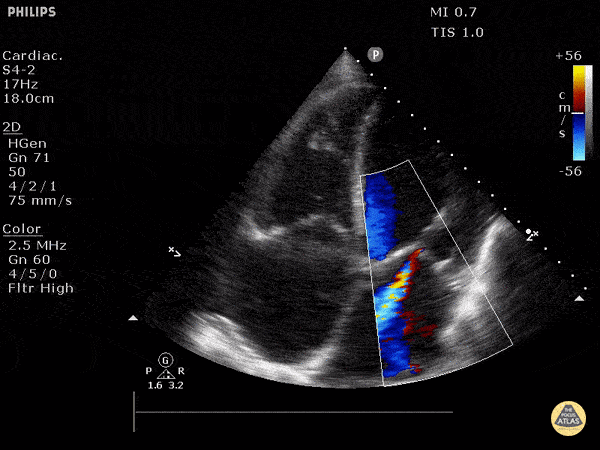

https://www.thepocusatlas.com/valvulopathy

View: Unspecified Parasternal Long Axis Parasternal Short Axis Apical Four-Chamber Subcostal Four-Chamber Subcostal Inferior Vena Cava Right Upper Quadrant Left Upper Quadrant Suprapubic Longitudinal Suprapubic Transverse Subxiphoid Anterior Thoracic Phrenic